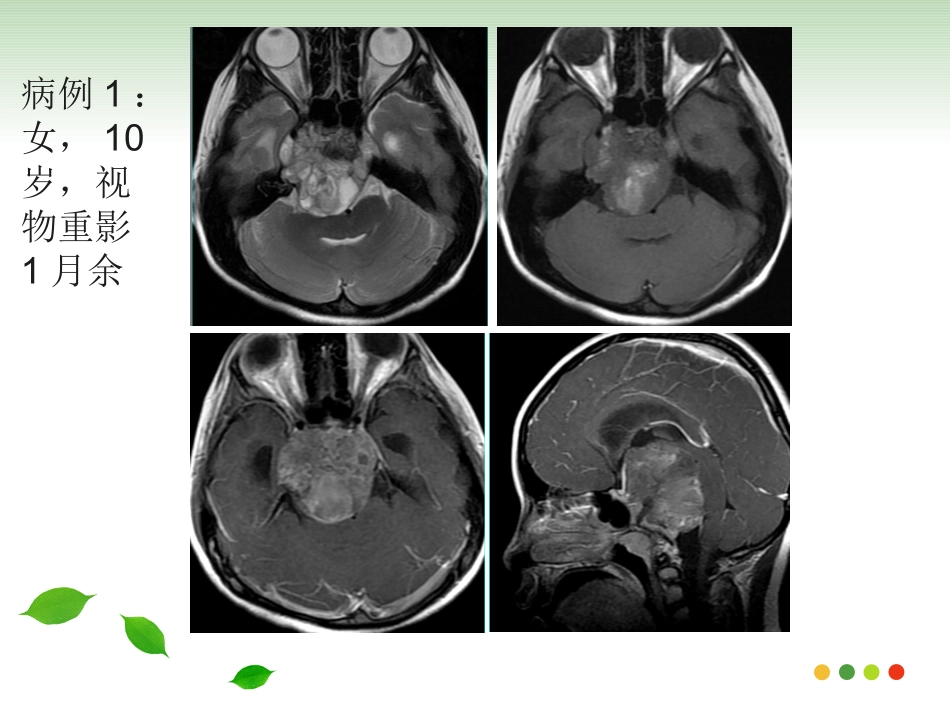

病例1:女,10岁,视物重影1月余病例2:男,47岁,视物重影2年余病例一病例二斜坡脊索瘤的影像诊断斜坡脊索瘤的影像诊断福建医科大学附属第一医院影像科2017级周晓芳发病机理发病机理•脊索是人体脊柱的原基,形成于胚胎期的第3周,上方由头盖骨的Rathke’s袋限制在蝶骨,向下和咽部相连,接着穿过齿状突和椎体中央•胚胎发育成为颅底的一部分和脊柱,残存的脊索组织可发展成为脊索瘤。概述概述•脊索瘤是一种比较少见的来源于脊索胚胎残余物的低度恶性肿瘤。•占颅内肿瘤的1%,占所有原发性骨肿瘤的4%•斜坡由枕骨基底部和蝶骨体共同组成,上界为鞍背,下界为枕骨大孔前缘,分上、中或下区。上区相当于蝶骨体,中区为蝶枕软骨结合处,下区为枕骨基底部,以中区最多见临床表现临床表现•可发生于任何年龄,成年人多见,30-40为高峰•男女比例2:1•生长缓慢,症状隐匿•最常见复视、颅神经麻痹及头痛;外展神经受累最常见,头痛通常在枕部或眶后位置病理表现病理表现•光镜下脊索瘤细胞胞浆丰富、内含黏液和大量空泡,也称液滴细胞;瘤细胞呈索条样分布,其间可见大量的黏液基质。•分为两个亚型:以液滴细胞为主、缺少软骨成分者为经典型;局灶性的软骨组织点缀在肿瘤基质内即为软骨瘤样型,软骨成分含量不一。治疗及预后治疗及预后•手术切除,辅以放射治疗•远处转移罕见,7%-14%可发生肺,肝,骨或淋巴结转移•5年生存率为60%〜70%•软骨瘤型预后更好,且软骨含量越高,预后越好。局部复发远处转移影像表现-CT影像表现-CT•大小不一,多在2-5cm之间•位于中心,广泛溶骨破坏•钙化不规则,通常被认为代表骨质破坏而不是肿瘤本身的营养不良钙化。•中度至显著强化,可见无强化粘液区影像表现-MRI影像表现-MRI•T1WI呈低信号,T2WI为明显高信号,软骨瘤型T2WI信号较低•常信号不均,可为陈旧出血、钙化、高蛋白粘液、纤维间隔或死骨•中至显著“蜂窝状”样、渐进性强化•邻近血管受压推移或部分包绕,但很少狭窄肿瘤扩散肿瘤扩散女,66岁,右眼视物模糊4年,右眼睑下垂半年女,66岁,右眼视物模糊4年,右眼睑下垂半年女,59岁,双眼视物模糊10余天女,59岁,双眼视物模糊10余天男,14岁,头痛伴反应迟钝、记忆力下降3个月男,14岁,头痛伴反应迟钝、记忆力下降3个月鉴别诊断鉴别诊断•软骨肉瘤•鼻咽癌•侵袭性垂体瘤•脑膜瘤•转移瘤软骨肉瘤软骨肉瘤•间叶源性肿瘤•偏中心性生长,中心多位于岩枕裂,或鞍旁•信号与脊索瘤相似,强化常轻微,可为结节状、分隔状及弥漫样•ADC值较高•钙化呈点、环、弧形男,47岁,视物双影2年余男,47岁,视物双影2年余鼻咽癌鼻咽癌•中心以鼻咽部为主,一侧或双侧咽隐窝的变浅消失,局部可见偏侧软组织肿块形成•T1WI呈等信号,T2WI信号稍高,强化明显•骨质破坏偏向一侧,肿瘤内缺乏钙化•颈部淋巴结肿大•临床鼻咽部的组织活检可明确诊断女,75岁,发现左颈部肿物1月余女,75岁,发现左颈部肿物1月余侵袭性垂体瘤侵袭性垂体瘤•T1WI为等信号,T2WI为等-高信号,常出血、坏死及囊变液液平多见•向鞍上生长明显时,可见束腰征,CT显示蝶鞍扩大,鞍底下陷,骨质破坏吸收•增强扫描明显强化,正常垂体不存在•易出现内分泌疾病的症状女,47岁,视物模糊1月余女,47岁,视物模糊1月余脑膜瘤脑膜瘤•CT均匀等密度,MR信号与脑实质相近•多以宽基底与颅骨相邻,明显均匀强化,硬脑膜尾征•骨质增生硬化,而骨质破坏少见男,47岁,左眼视物不清半年转移瘤转移瘤•原发病史,常为多发•T2WI呈等或低信号,肿瘤内缺乏钙化•骨质破坏较软组织肿块范围大女,46岁,肺癌病史小结小结•30-40为高峰,最常见复视、颅神经麻痹及头痛•肿瘤多在2-5cm之间•边界清楚,不规则型及分叶状多见•溶骨性破坏•T2WI为明显高信号•中度至显著强化,呈蜂窝样、颗粒样且持续强化•邻近血管受压推移或部分包绕,但很少狭窄